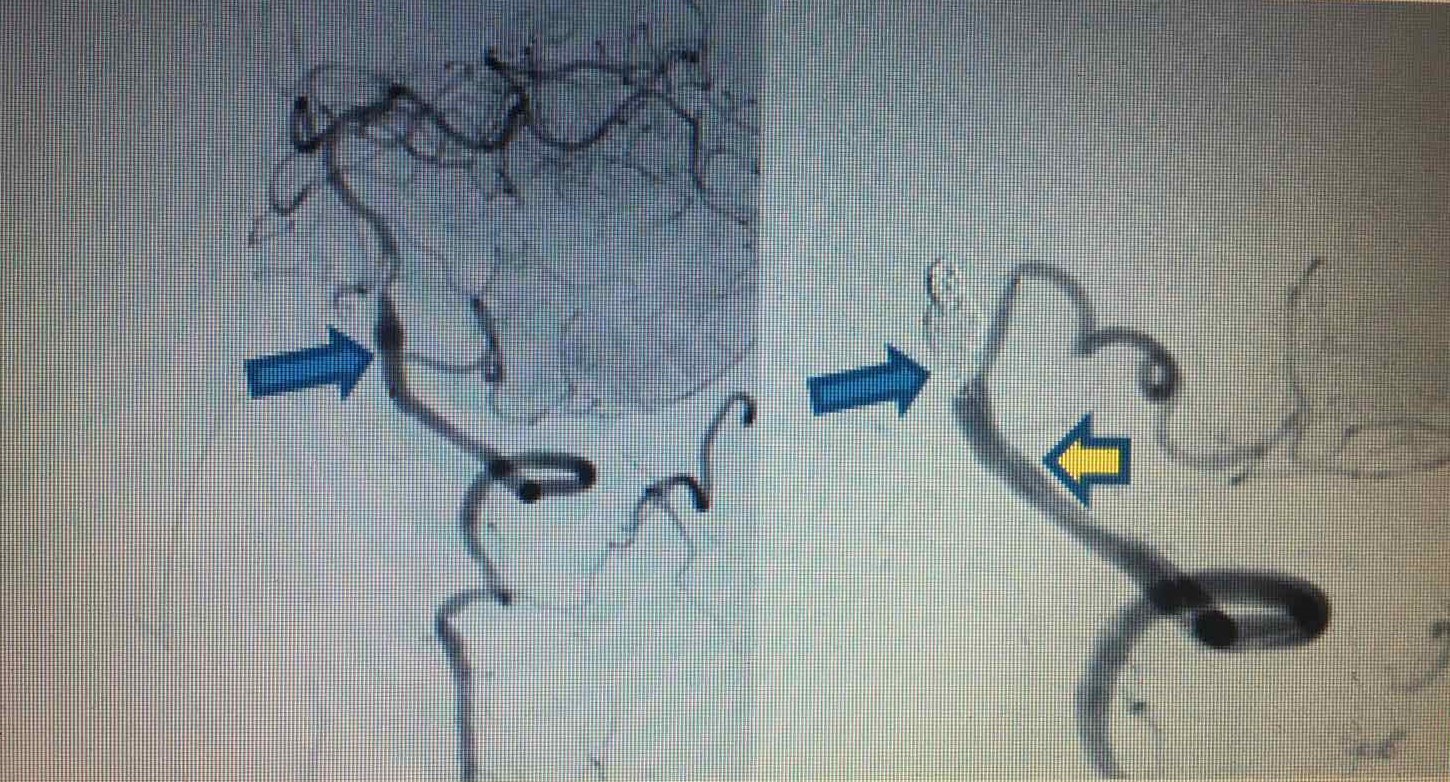

Hình ảnh trước và sau can thiệp (trái: Phình hình thoi bóc tách động mạch) và (phải: Đặt stent động mạch đốt sống - PICA trái và bít coils tắc hoàn toàn phình hình thoi) |

Chiều 4/4/2020, ông Tr. Q. T. (57 tuổi, ở Hà Nội) phải nhập viện do đột quỵ não tái phát. Kết quả chụp CT mạch máu não cho thấy ông T. bị phình hình thoi do bóc tách động mạch đốt sống trái lan vào gốc PICA trái. Kíp can thiệp bệnh viện Vinmec Times City đã tiến hành can thiệp đặt stent loại bỏ phình mạch não.

Trước đó, lần đột quỵ đầu tiên của ông T. xảy ra vào chiều ngày 20/3/2020 và đã được cấp cứu kịp thời tại BV Vinmec Times City với chẩn đoán tắc hoàn toàn động mạch đốt sống trái, tắc gốc PICA cùng bên gây nhồi máu cấp tính thùy nhộng và bán cầu tiểu não trái. Lúc đó, người bệnh đã được các bác sĩ chỉ định lấy huyết khối cơ học động mạch não DSA ở giờ thứ 3. “Ưu tiên trong lúc đó là giải quyết phần “ngọn” để cứu tính mạng người bệnh, bởi thời gian can thiệp quá dài có thể quá sức chịu đựng của người bệnh trong bối cảnh đó. Do đó, trong hơn 1h đồng hồ, kíp can thiệp đã tiến hành hút huyết khối, nong bóng qua chỗ hẹp bóc tách và gốc PICA trái để khơi thông được mạch đang bị tắc nghẽn” - ThS.BS Vũ Huy Hoàng, Khoa Chẩn đoán hình ảnh, Bệnh viện Vinmec Times City, người trực tiếp can thiệp cho ông T. chia sẻ.